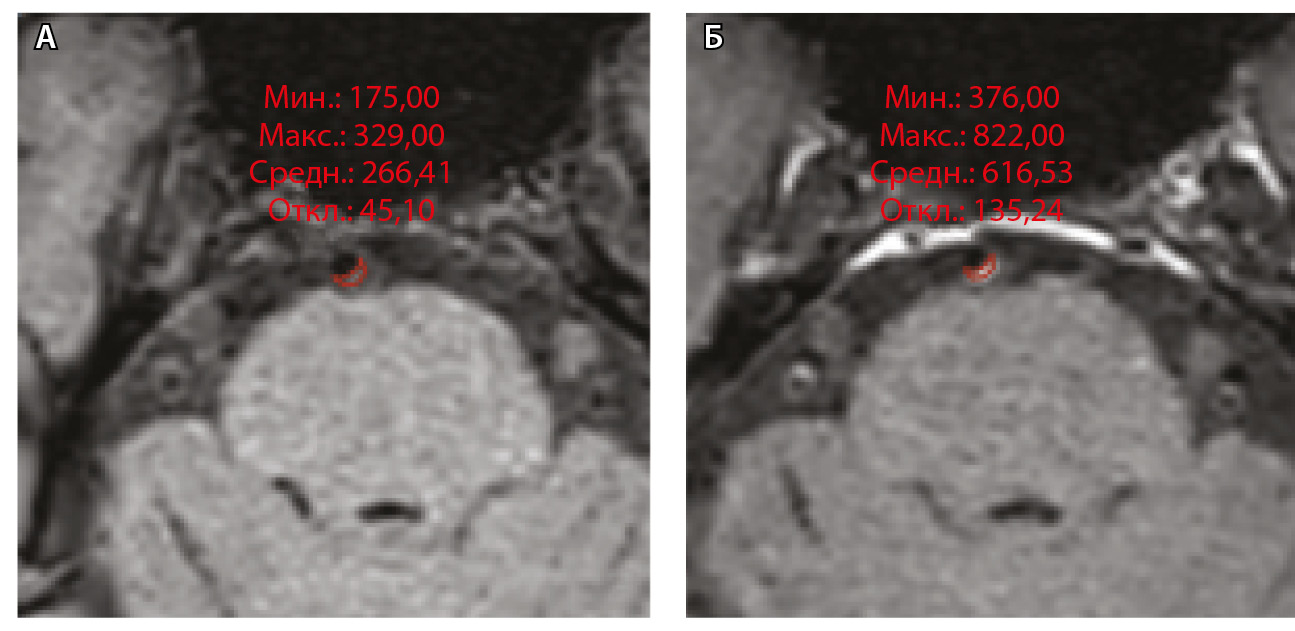

Для количественной оценки степени накопления контрастного вещества в области интереса (АСБ, неизмененная сосудистая стенка, воронка гипофиза) рассчитывали WEI по формуле:

где WEI (wall enhancement index) – индекс усиления контрастности стенки (сосудов), SIwallprecontrast – интенсивность сигнала (Signal Intensity, SI) сосудистой стенки (wall) в зоне интереса на преконтрастных (precontrast) изображениях, SIwallpostcontrast – интенсивность сосудистой стенки в зоне интереса на постконтрастных (postcontrast) изображениях; SIbrainprecontrast – интенсивность неизмененного белого вещества мозга (brain) на доконтрастных изображениях; SIbrainpostcontrast – интенсивность неизмененного белого вещества мозга на постконтрастных изображениях. Пример измерения интенсивности сигнала от АСБ для расчета WEI приведен на рисунке 1.

Рис. 1. Пример измерения интенсивности эхо-сигнала от атеросклеротической бляшки базилярной артерии для расчета индекса усиления контрастности стенки сосуда (WEI). В месте максимального стеноза артерии на одном срезе отмечали область интереса (ROI) и регистрировали среднее значение интенсивности сигнала от сосудистой стенки (SIwall). ROI были сопоставлены по размеру и местоположению в наборе данных T1-TSE-db-FS до (А) и после (Б) контрастного усиления; макс. – максимум, мин. – минимум, откл. – отклонение, средн. – среднее